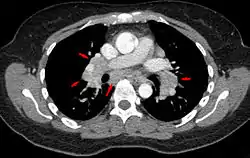

Hilar adenopathy especially on the person's left (AP CXR)

Hilar adenopathy especially on the person's left (lateral CXR)

Hilar adenopathy especially on the person's left (coronal CT)

Hilar adenopathy especially on the person's left (transverse CT)